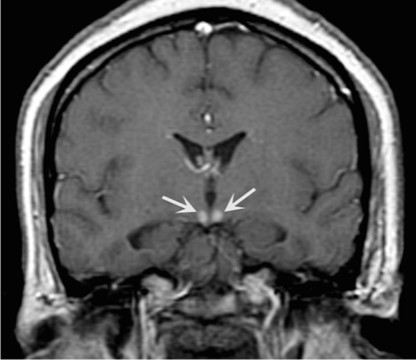

Витамин В1 является кофактором нескольких ферментов (транскетолазы, альфа-кетоглутаратдегидрогеназы, пируватдегидрогеназы). При недостатке витамина В1 снижается утилизация глюкозы нейронами, повреждаются митохондрии. Накопление глутамата вследствие снижения активности альфа-кетоглутаратдегидрогеназы оказывает нейротоксическое действие. Поражаются перивентрикулярные отделы ствола мозга, промежуточного мозга, верхняя часть червя мозжечка. Частые признаки - демиелинизация, пролиферация эндотелия, распад нейропиля, гибель части нейронов. Возникновение амнезии связывают с поражением медиодорсального ядра таламуса.

- магнитно-резонансная томография головного мозга;